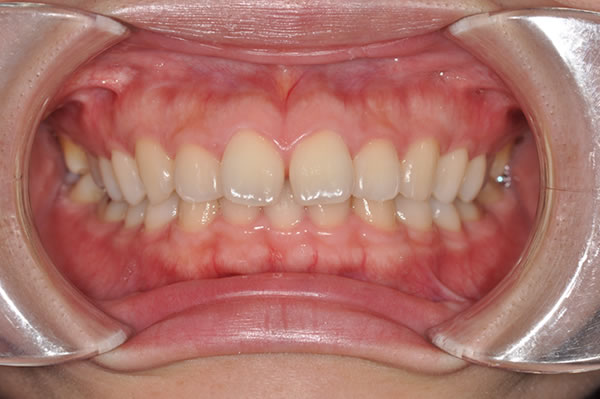

上顎前突症の治療例

上顎前突症(出っ歯)の矯正症例 ケース02

| 治療前(初診) | 治療後 | |